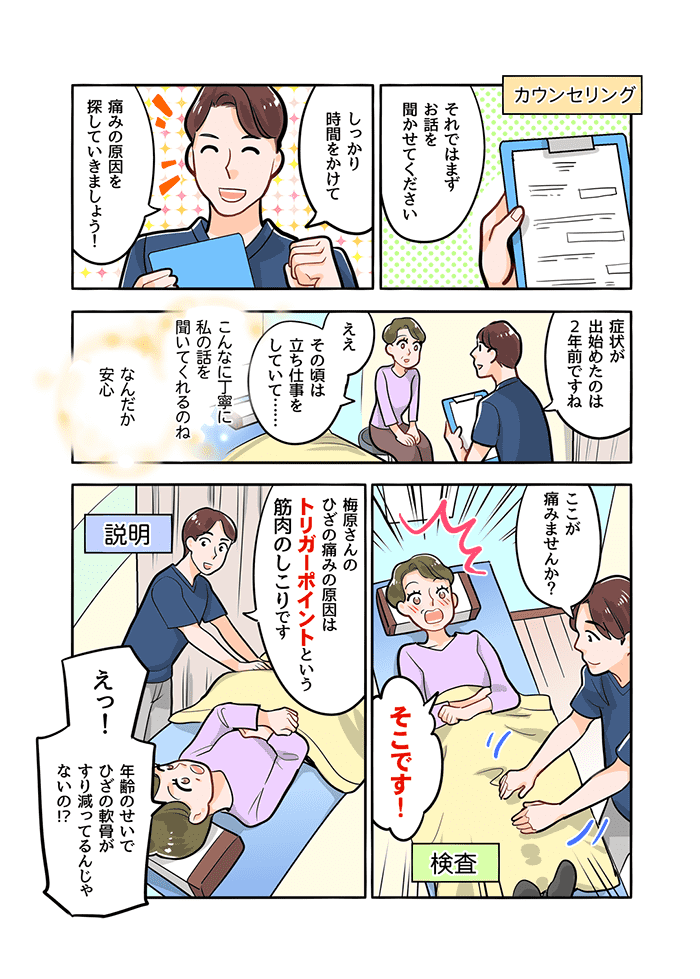

膝に痛みを感じる筋肉の状態とは?筋肉が硬くなると膝に痛みを感じるのか・・・?

これは半分正解で半分不正解です。

筋肉は硬くなっただけでは痛みを感じません。

筋肉内にトリガーポイントが発生すると痛みを感じます。

トリガーポイントとは、筋肉内におこる筋肉のしこりです。

筋肉に幾度となく負担がかかり続けると、筋肉内で血流障害が起こります。

その結果、筋肉内に十分な栄養素や酸素が供給されずトリガーポイントというしこりが発生します。

膝の変形が直接痛みを引き起こすのではなく、負担がかかりやすい膝の構造状態で生活することにより、膝周りの筋肉に過剰に負担が加わりその結果筋肉内にトリガーポイントが生じて膝に痛みを引き起こすのです。

膝の痛みを解消するためには膝の変形を治すことではなく、膝の変形によって膝の筋肉にかかって発生したトリガーポイントを改善することが痛みを取り除くには最善の方法なのです。

下記図は膝を安定させるために大いに働く大腿四頭筋という筋肉にトリガーポイントが発生した際に痛みの出る範囲です。図からもわかるように膝の内側などを中心に痛みを感じます。※専門用語で関連痛と言います。